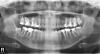

carapuz95 Опубликовано 21 июля, 2011 Поделиться Опубликовано 21 июля, 2011 Добрый день, уважаемые форумчане и специалисты! Требуется Ваша помощь!Начну из далека: мне 25 лет, с самого детства врач-стоматолог был всегда моим любимым врачом, т.к. я его очень часто посещал. У меня всегда была плохая эмаль на зубах, и из-за этого постепенно рушились зубы. К 25 годам половина челюсти уже переделано, особенно "жевательные" зубы. Сейчас решил заняться зубами вплотную, посетил двух врачей и у обоих разное мнение, один говорит что нижних две 6-ки, и 5-ку нужно удалять поскольку под ними имеется киста. А другой врач уверяет, что сможет вылечить эту кисту и остаться с зубами. И оба говорят, что нужно однозначно ставить коронкиВопросы:1. Действительно можно вылечить их?2. Нужно ли ставить коронки? P.S. Снимок прилагаю. Ссылка на комментарий

Alisa st Опубликовано 21 июля, 2011 Поделиться Опубликовано 21 июля, 2011 Нижняя семерка слева очень сомнительный зуб. В любом случае надо пробовать перелечить прежде чем удалять. Ссылка на комментарий